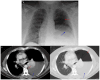

Coccidioidomycosis is a disease caused by soil fungi of the genus Coccidioides, divided genetically into Coccidioides immitis (California isolates) and Coccidioides posadasii (isolates outside California). Coccidioidomycosis is transmitted through the inhalation of fungal spores, arthroconidia, which can cause disease in susceptible mammalian hosts, including humans. Coccidioidomycosis is endemic to the western part of the United States of America, including the central valley of California, Arizona, New Mexico, and parts of western Texas. Cases have been reported in other regions in different states, and endemic pockets are present in these states. The incidence of reported cases of coccidioidomycosis has notably increased since it became reportable in 1995. Clinically, the infection ranges from asymptomatic to fatal disease due to pneumonia or disseminated states. The recognition of coccidioidomycosis can be challenging, as it frequently mimics bacterial community-acquired pneumonia. The diagnosis of coccidioidomycosis is frequently dependent on serologic testing, the results of which can take several days or longer to obtain. Coccidioidomycosis continues to present challenges for clinicians, and suspected cases can be easily missed. The challenges of coccidioidomycosis disease, from presentation to diagnosis to treatment, remain a hurdle for clinicians, and further research is needed to address these challenges.